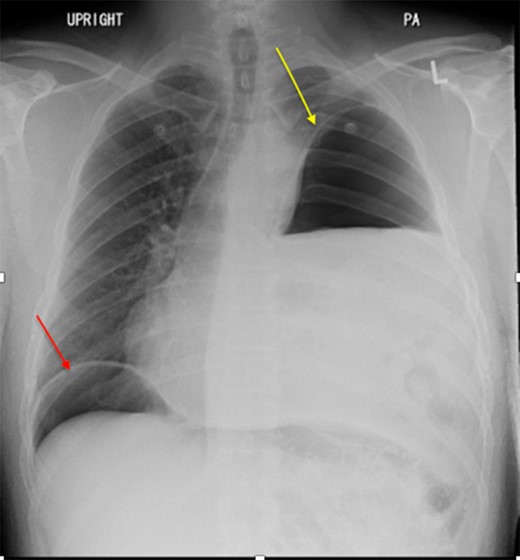

We present a 44-year-old male patient came to the emergency department complaining of right upper quadrant abdominal pain. The patient reported taking over-the-counter (OTC) ibuprofen intermittently for a past few months due to backaches. His past medical history is only positive for falling off a 15 feet ladder at the age of 15 years old. Upon examination, he had right upper quadrant abdominal tenderness, a heart rate of 90 beats/min and a respiratory rate of 20 breaths/min on room air. The patient clinical status was stable and looked well. Chest x-ray showed a moderate left hemidiaphragm elevation with bowel contents overlying the left chest (Fig. 1). Of note, a large amount of air inferior to the right hemidiaphragm was indicative for pneumoperitoneum. Laboratory investigations were immediately carried out and revealed a white blood cell count (WBC) of 4.5 × 109/L (normal range: 4–11 × 109/L). The WBC remained at the normal level until the end of the patient’s admission. Further imaging studies were ordered due to the peculiar coexistence of x-ray findings and stable clinical status. The computed tomography (CT) scan showed a contracted left lung with severe volume loss and just mild aeration of the left upper lung (Fig. 2). No definite left pneumothorax was seen. The majority of the left hemithorax was filled with abdominal contents including the stomach, spleen, pancreatic tail, left kidney, splenic flexure of the colon, and small bowel loops. A small hypodense focus was observed within the intra-thoracic stomach and extended to the stomach wall, with mild adjacent stranding of fat and a small amount of free fluid. We suspected the presence of perforated gastric ulcer secondary to non-steroidal anti-inflammatory drugs (NSAIDs) usage. The upper gastrointestinal (GI) series was performed and did not show any extravasation, indicating that there was some other source or the gastric perforation had walled off. The patient was thus managed conservatively; his diet was advanced and the patient discharged home on Day 4.

CT scan showing collapse of left lung and left diaphragmatic hernia.